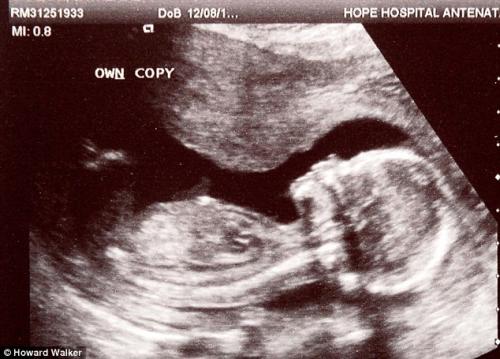

На Catherine Urhegyi на контролниот ултразвук и ги кажале најлошите вести, кои може да ги слушне една мајка: бебето починало. Уште и кажале треба да се обидат да предизвикаат абортус за да избегнат киретажа.

На Кетрин и понудиле три опции: да предизвикаат абортус со медикаменти, да направат киретажа или пак да чекаат спонтано да го исфрли плодот, што можело да потрае со недели. Парот се согласил да се обидат да предизвикаат абортус. Два дена откако ги испила пилулите, Кетрин добила тешко крварење и се вратила во болница за да се доврши абортусот. На запрепрастување на сите, ултразвукот покажал дека бебето е живо и дека има срцева акција.

Сосема неочекувано малото девојче го преживеало лошиот совет за абортус. Парот сега е во агонија очекувајки бебето да се роди и да се осигураат дали пилулите не предизвикале некакво оштетување кај нивната ќерка.

Лекарите ги предупредиле родителите дека не можат да бидат сигурни дали малото девојче нема да има вродени дефекти, заради абортицифиентот - кој бил администриран во периодот на критичните 12 недели на развојот на бебето. Парот решил јавно да проговори за нивното искуство во надеж дека болниците ќе се осигурат да извршат и втор ултразвучен преглед доколку се сомневаат дека бебето починало во матката.